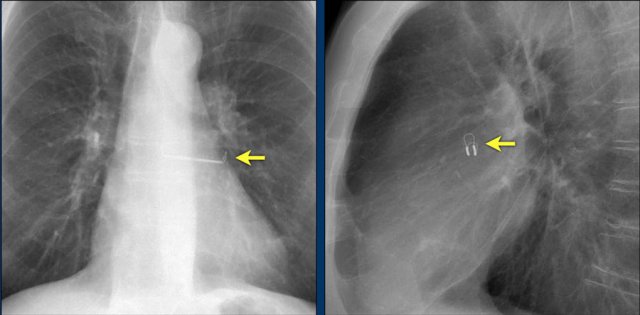

The images show a pacemaker with an atrial and ventricular lead.

The tip of the atrial lead is pointed upward and anteriorly, because the ideal position is in the right atrial appendage, where it is anchored within the coarse trabeculae.

The tip of the ventricular lead is positioned in the apex of the right ventricle, which is located to the left of the spine on a frontal chest X-ray and anteriorly on a lateral view.